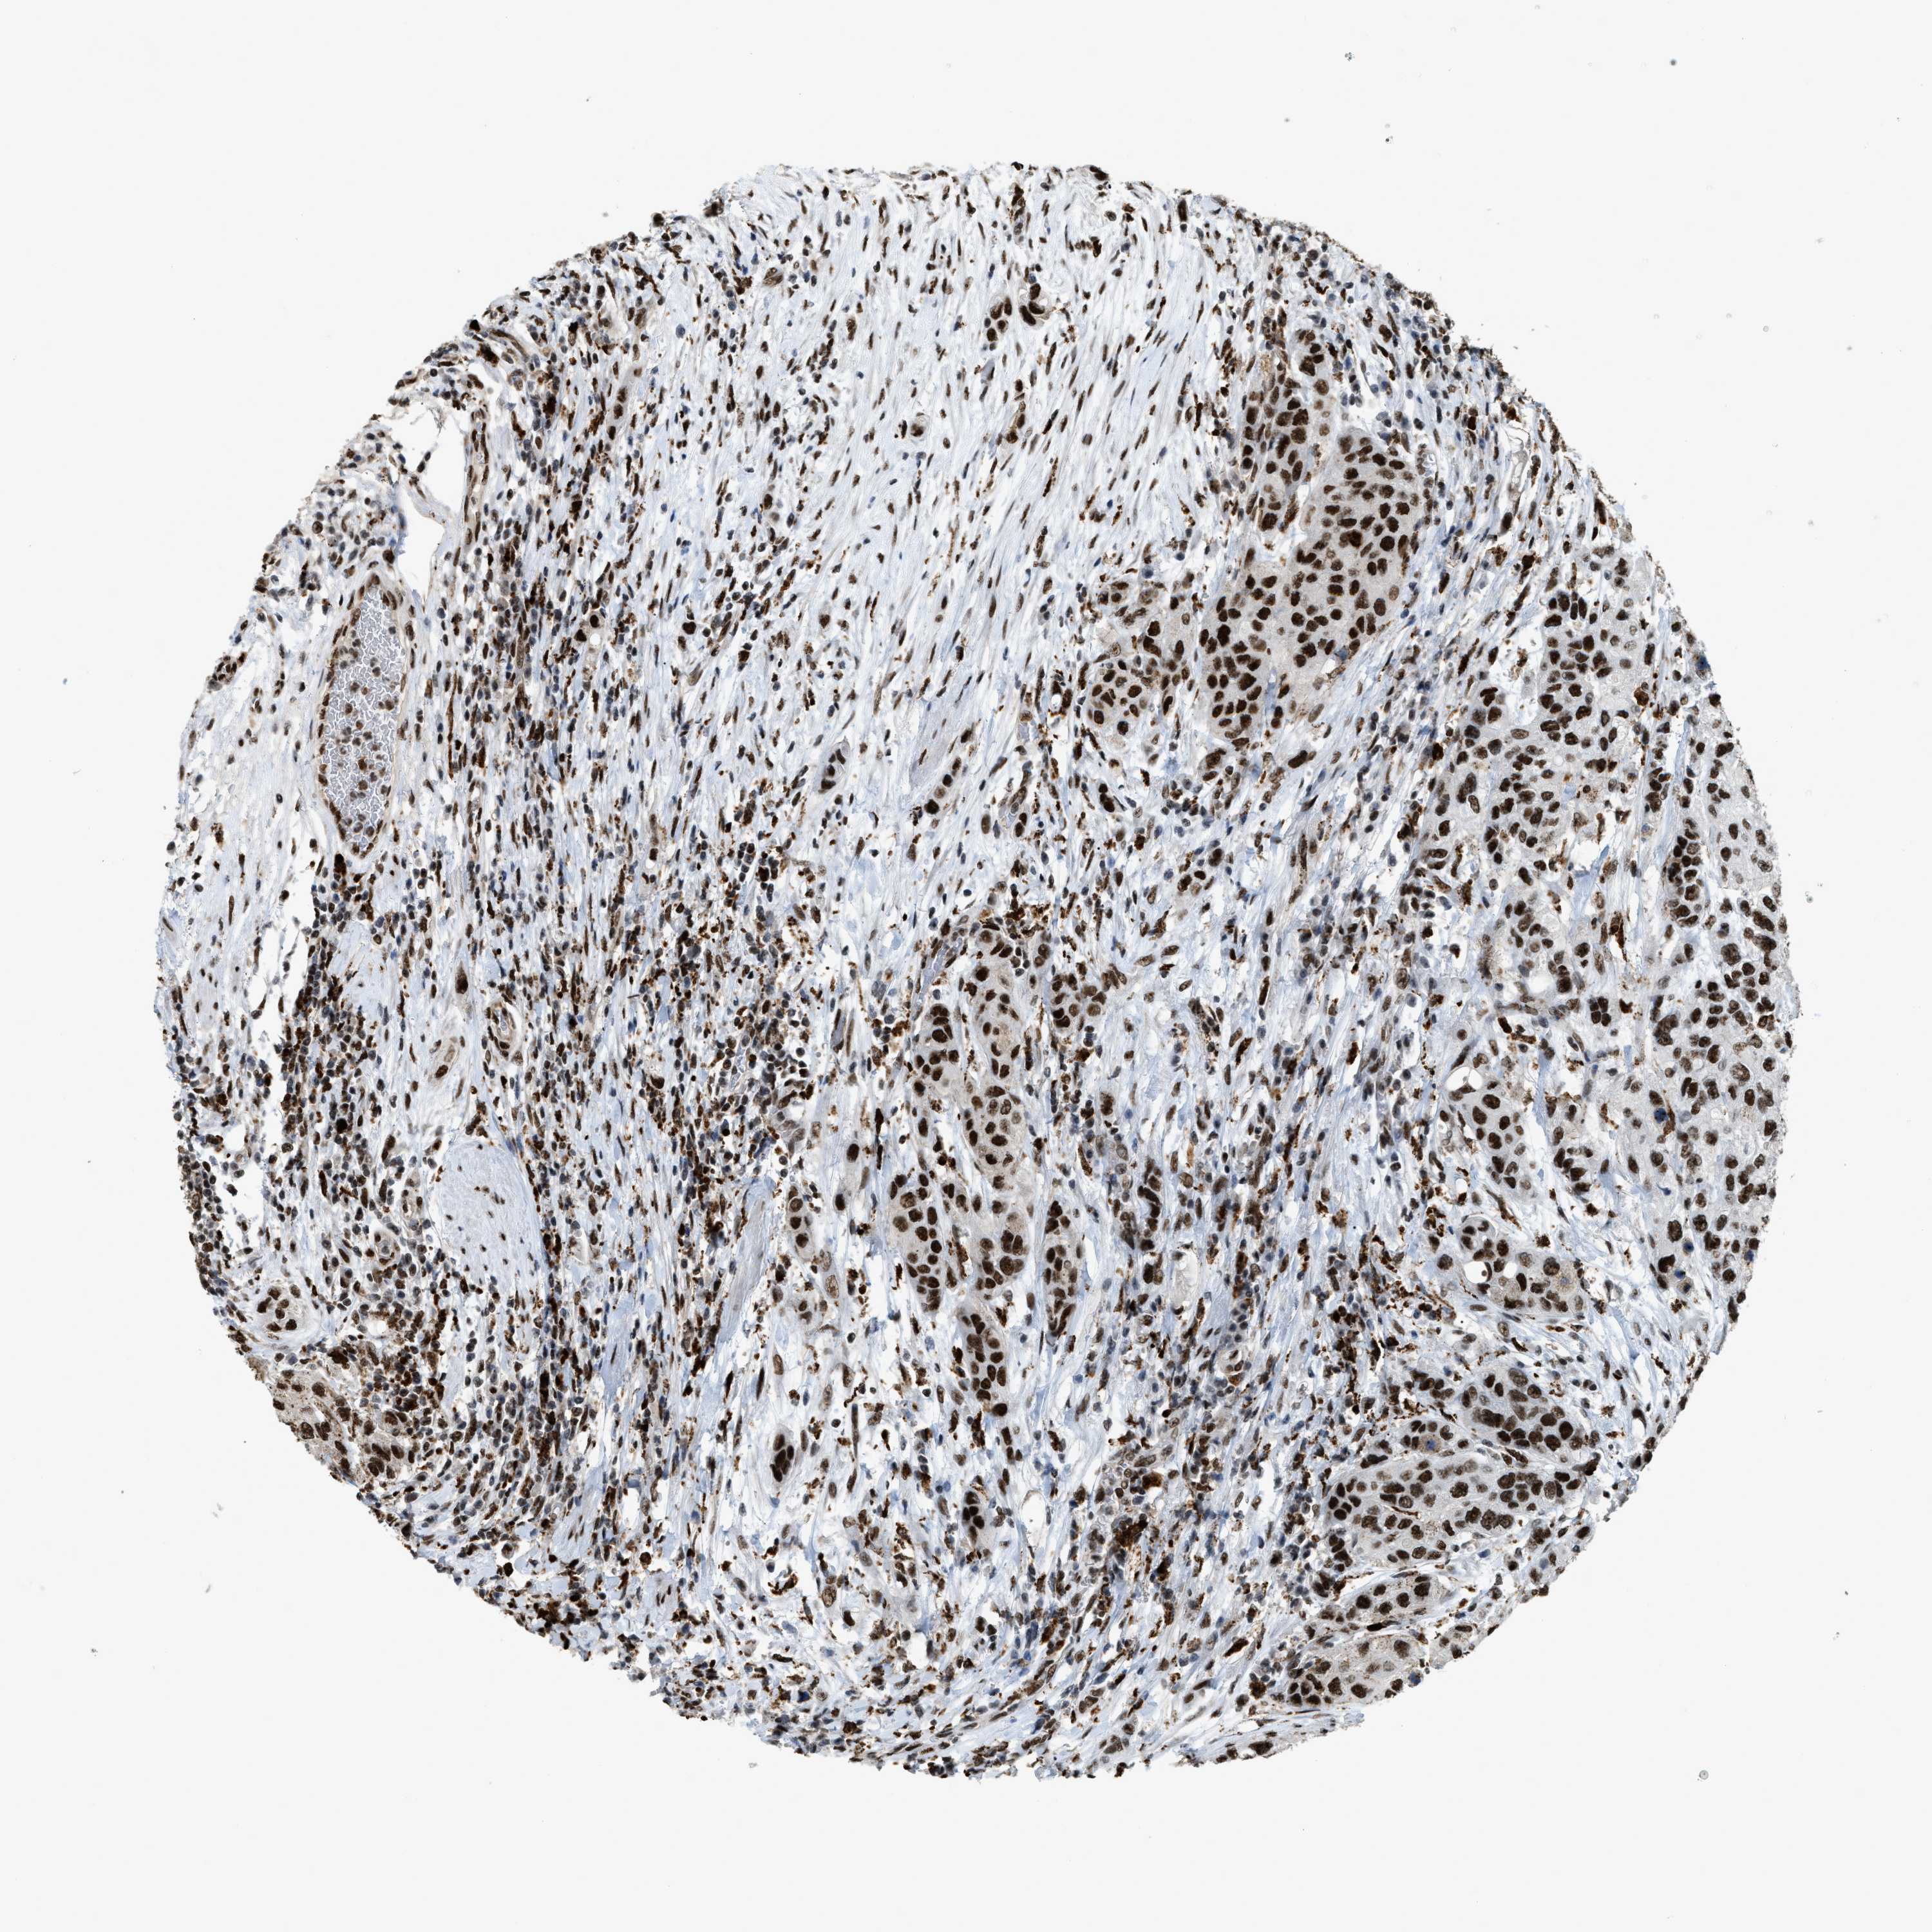

UROTHELIAL CANCER - Protein expressioni

A mouse-over function shows sample information and annotation data. Click on an image to view it in a full screen mode. Samples can be filtered based on level of antibody staining by selecting one or several of the following categories: high, medium, low and not detected. The assay and annotation is described here.

Note that samples used for immunohistochemistry by the Human Protein Atlas do not correspond to samples in the TCGA dataset.

Antibody stainingi

Antibody staining in the annotated cell types in the current human tissue is reported as not detected, low, medium, or high, based on conventional immunohistochemistry profiling in selected tissues. This score is based on the combination of the staining intensity and fraction of stained cells.

Each image is clickable and will lead to virtual microscopy that enables deeper exploration of all samples and also displays staining intensity scores, fraction scores and subcellular localization as well as patient and tissue information for each sample.

Antibody HPA019841

Antibody HPA019859

Antibody HPA029912

Staining

High

Medium

Low

Not detected

Intensity

Strong

Moderate

Weak

Negative

Quantity

>75%

75%-25%

<25%

None

Location

Nuclear

Cytoplasmic/membranous

Cytoplasmic/membranous,nuclear

Urothelial carcinoma, Low grade

Urothelial carcinoma, High grade